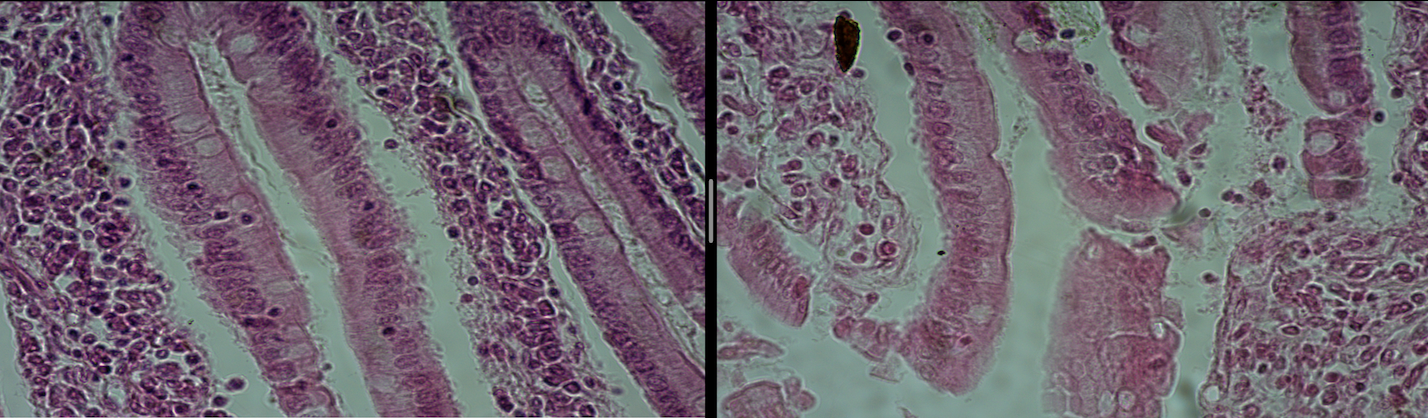

Small Intestine

Small Intestine mucosa

Large Intestine

Large Intestine mucosa

Ileum

Microvilli